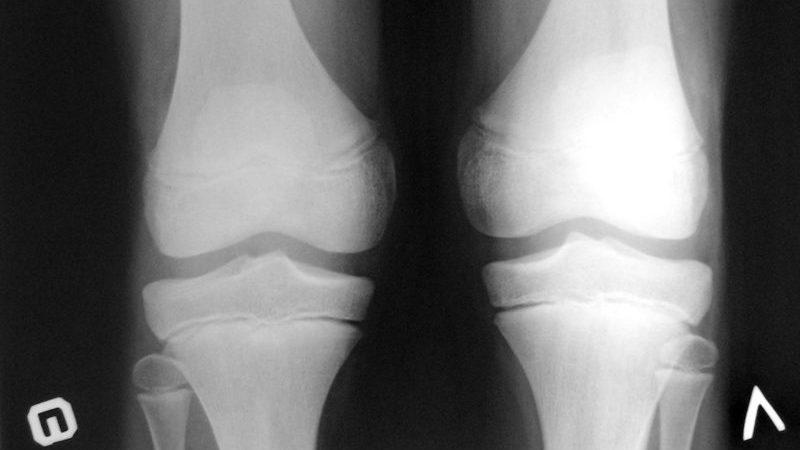

Самостоятельная постановка диагноза может быть опасной. Только квалифицированный врач, основываясь на симптомах и стадии заболевания, сможет выбрать наиболее подходящие методы диагностики. Существует пять основных методов диагностики:

- Ультразвуковое исследование (УЗИ) должно проводиться исключительно опытным специалистом. Он способен получить точную картину заболевания. Данный метод с высокой вероятностью позволяет выявить болезнь и определить ее стадию.

- Сцинтиграфия. Этот метод обладает высокой эффективностью, однако не применяется для диагностики у детей. С его помощью можно определить заболевание на всех трех стадиях.

- Магнитно-резонансная томография (МРТ). Этот метод позволяет детально исследовать сустав, пораженный болезнью Кенига. МРТ может выявить заболевание даже на ранних этапах. Она предоставляет объективную информацию о текущем состоянии сустава. Также результаты МРТ помогают подтвердить диагноз, а также отслеживать прогресс заболевания и возможные патологические изменения.

- Дифференциальная диагностика важна на начальных стадиях остеохондропатии.

- Артроскопия. Этот метод в основном используется для диагностики болезни Кенига и эффективен на всех трех стадиях заболевания. Артроскопия позволяет с высокой точностью установить диагноз, что в дальнейшем помогает выбрать наиболее подходящий и эффективный метод лечения.